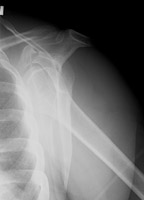

- Click on the image for a larger versionAAP radiograph of the left shoulder. In addition to the anterior dislocation of the humerus, there is irregularity of the coracoid process.